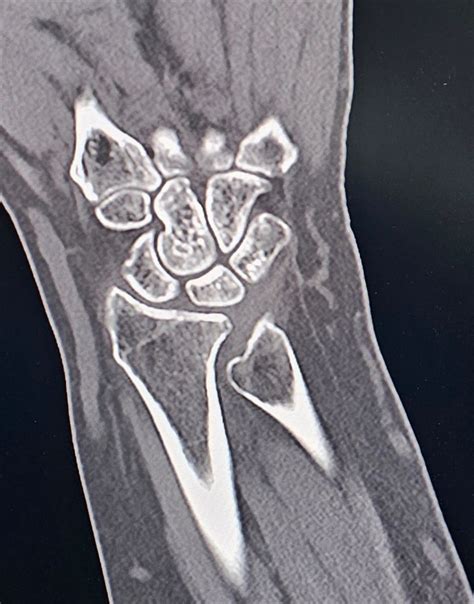

Imaging is equally vital. Standard X-rays, particularly those taken in a neutral position, help clinicians measure the ulnar variance. In more complex cases, an MRI is ordered to evaluate the extent of TFCC damage, cartilage wear on the lunate, or subchondral bone edema, which is the "bruising" of the bone caused by persistent impaction.